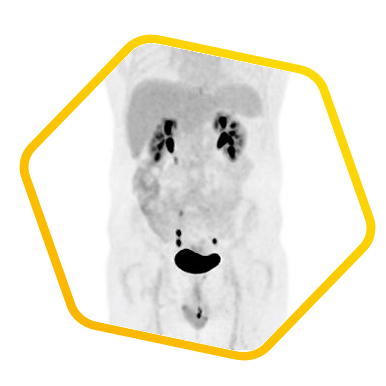

脑神经内分泌肿瘤

双示踪剂PET/CT (F-18 FDG及Ga-68 DOTATATE) 用於评估脑神经内分泌肿瘤体内的扩散情况

![]() [F-18] FDG |

![]() [Ga-68] DOTATATE |